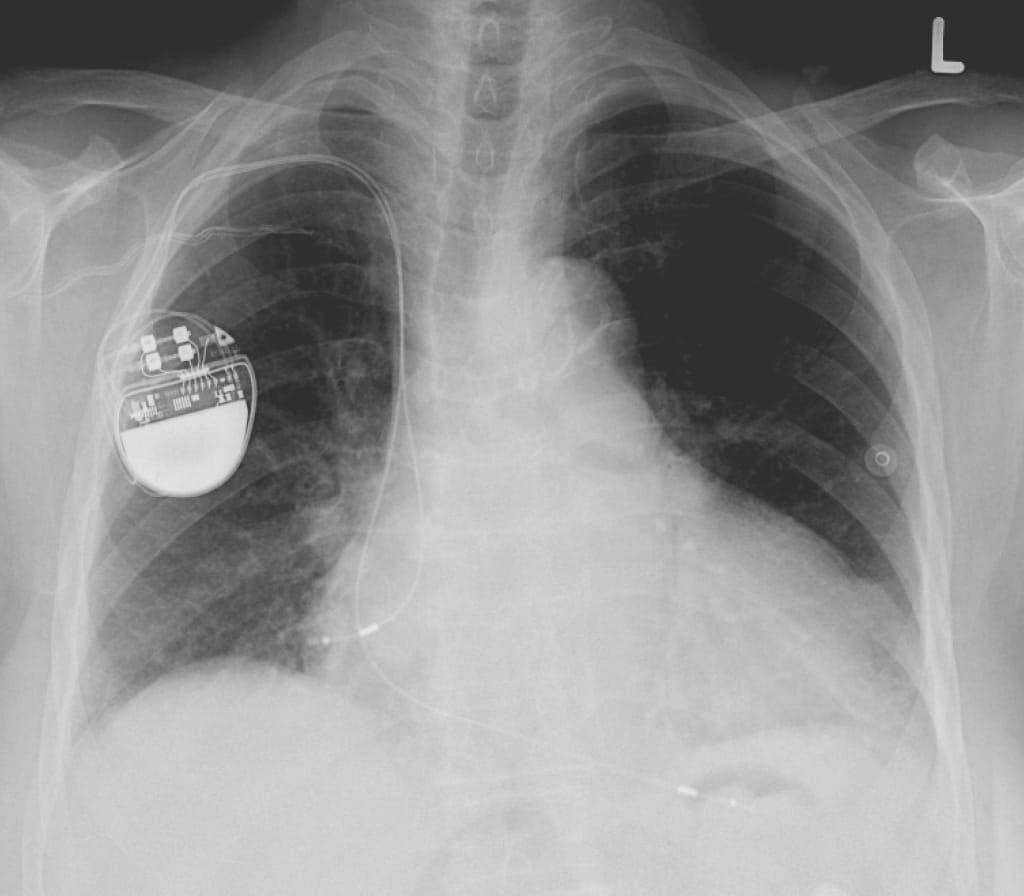

She felt a familiar hitch in her chest as the pacemaker her doctor had implanted shocked her heart into a normal rhythm.

Shirley picked up the magnet and made her way to the bed. She felt the jolt of her pacemaker again and felt a bit light-headed. She climbed into bed and rested the hand with the magnet on her chest, above her heart. After a minute she felt a twinge again, stronger, but no kick from her pacemaker.